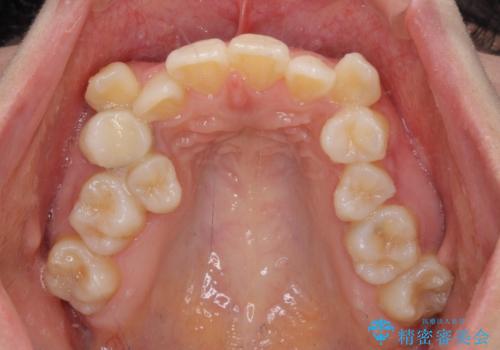

右側の上下は歯が重なり合って、内側に移動してしまうほどであり、それに伴って正中の位置が右側にずれている状態でした。

上下左右の第一小臼歯4本を抜歯して行うことになりますが、それだけでは咬み合わせの改善や正中位置の改善が困難であると判断されたため、アンカースクリューを用いた補助装置を併用することで、スムーズかつより良い仕上がりを目指すこととしました。